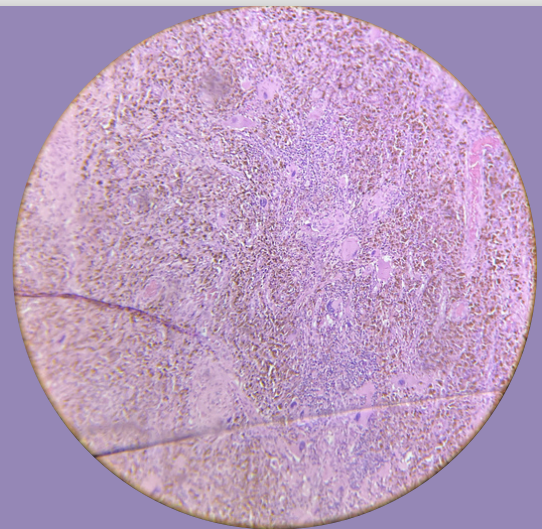

Sarcoma pleomórfico de alto grado:

Células pleomórficas, dispuestas en láminas con una relación N-C aumentada e hipercromasia importante, mitosis aumentada